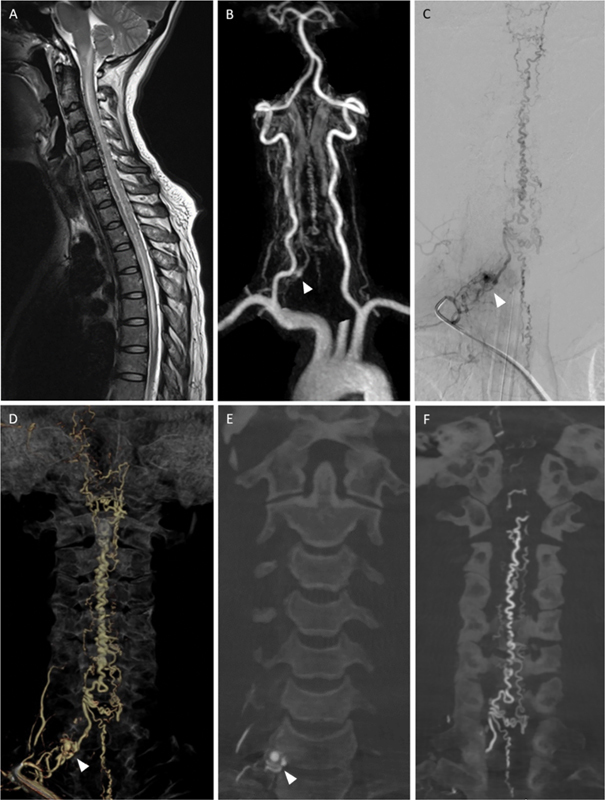

下颈动静脉瘘(AVFs)是一种罕见而复杂的血管畸形,由于其位置和表现多变,给临床带来了重大挑战。虽然上颈椎avf已被广泛研究,但下颈椎avf仍未得到充分研究。本研究旨在回顾下颈椎avf患者的临床表现、治疗策略和结果,以提高对治疗方法的认识和改进。我们对2006年6月至2023年12月期间在我院治疗的脊柱血管畸形患者进行了回顾性分析,确定了2例下颈椎avf。此外,采用Ovid MEDLINE、PubMed和Cochrane等数据库,按照系统评价和荟萃分析指南的首选报告项目,对44例下颈椎avf患者进行了系统文献综述。收集的数据包括患者人口统计学、临床表现、瘘管类型、动脉和静脉受累、治疗方式和神经预后。包括我们2例在内的44例下颈椎avf患者中,50%为女性,平均年龄48.68岁(范围4-76岁)。临床表现各不相同,27.3%出现出血,18.2%出现脊髓病,18.2%无症状。静脉引流方式在症状严重程度中起着重要作用,复杂的髓周静脉引流和逆行静脉引流会导致更差的结果。治疗方式包括血管内栓塞(40.9%)、手术切除(25%)和联合入路(18.2%),54.5%的病例恢复良好。下颈椎avf由于其不同的表现和复杂的血管解剖结构而面临多种临床挑战。早期诊断和量身定制的管理,包括血管内栓塞和手术切除,是优化患者预后的必要条件。需要进一步研究以更好地了解无症状房颤的自然史并改进治疗方案。

Lower cervical arteriovenous fistulas (AVFs) are rare and complex vascular malformations that pose significant clinical challenges due to their location and variable presentation. While upper cervical AVFs have been extensively studied, lower cervical AVFs remain underresearched. This study aims to review the clinical presentations, management strategies, and outcomes of patients with lower cervical AVFs to enhance understanding and improve treatment approaches. We conducted a retrospective analysis of patients with spinal vascular malformations treated at our institute between June 2006 and December 2023, identifying two cases of lower cervical AVFs. Additionally, a systematic literature review was performed following the Preferred Reporting Items for Systematic Reviews and Meta-Analyses guidelines, including 44 patients with lower cervical AVFs, using databases such as Ovid MEDLINE, PubMed, and Cochrane. Data collected included patient demographics, clinical presentation, fistula type, arterial and venous involvement, treatment modality, and neurological outcomes. Among the 44 patients with lower cervical AVFs, including our two cases, 50% were female, and the mean age was 48.68 years (range: 4-76 years). Clinical presentations varied, with 27.3% experiencing hemorrhage, 18.2% presenting with myelopathy, and 18.2% remaining asymptomatic. Venous drainage patterns played a significant role in symptom severity, with complex perimedullary and retrograde venous drainage contributing to worse outcomes. Treatment included endovascular embolization (40.9%), surgical resection (25%), and combined approaches (18.2%), with good recovery achieved in 54.5% of cases. Lower cervical AVFs present diverse clinical challenges due to their variable presentations and complex vascular anatomy. Early diagnosis and tailored management, including endovascular embolization and surgical resection, are essential for optimizing patient outcomes. Further research is needed to better understand the natural history of asymptomatic AVFs and improve treatment protocols.